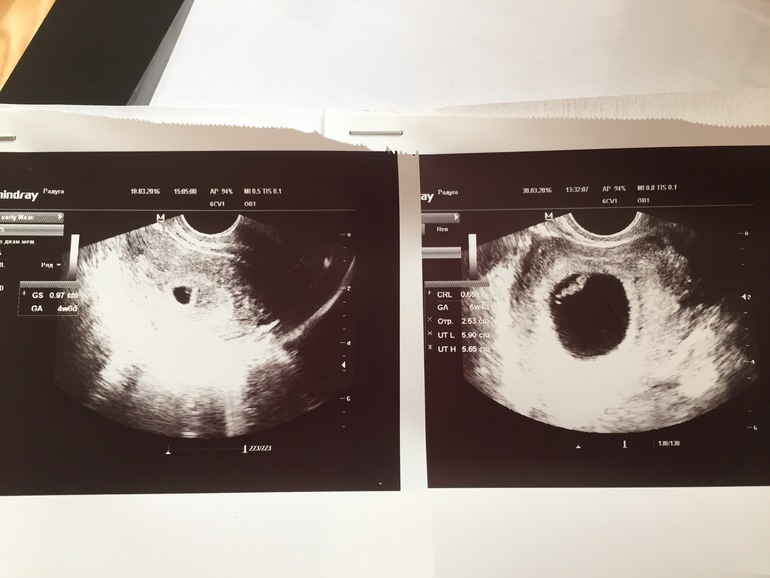

Вот и я сходила на узи

Сходила, эмбрион 6,5мм, срок аппарат поставил 6+4, все по плану, сердцебиение засняла на видео) Сколько по показателям ничего не спрашивала, я у нее давно наблюдаюсь, сказала все отлично, все нравится)) ну и я довольна соответственно)(первое узи на фото это 12 дней назад, срок 4+6, второе - сегодня 6+4)

Можете посмотреть фото УЗИ в дневнике у меня